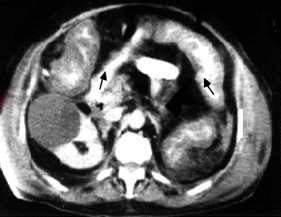

- טומוגרפיה ממוחשבת — מראה את הכרכשת הפגועה, התכייבויות והרס הרירית (תצלום 18.6).